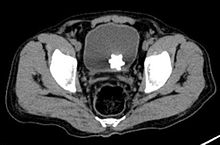

Large jackstone in the bladder of a 60-year-old Middle Eastern man. Stone was removed by open cystolithotomy.

A star-shaped Jackstone urolith can be seen in the urinary bladder on this radiograph of the pelvis

Jackstone calculi are rare bladder stones that have an appearance resembling toy jacks. They are almost always composed of calcium oxalate dihydrate and consist of a dense central core and radiating spicules. They are typically light brown with dark patches and are usually formed in the urinary bladder and rarely in the upper urinary tract. Their appearance on plain radiographs and computed tomography in human patients is usually easily recognizable. Jackstones often must be removed via cystolithotomy.[10]